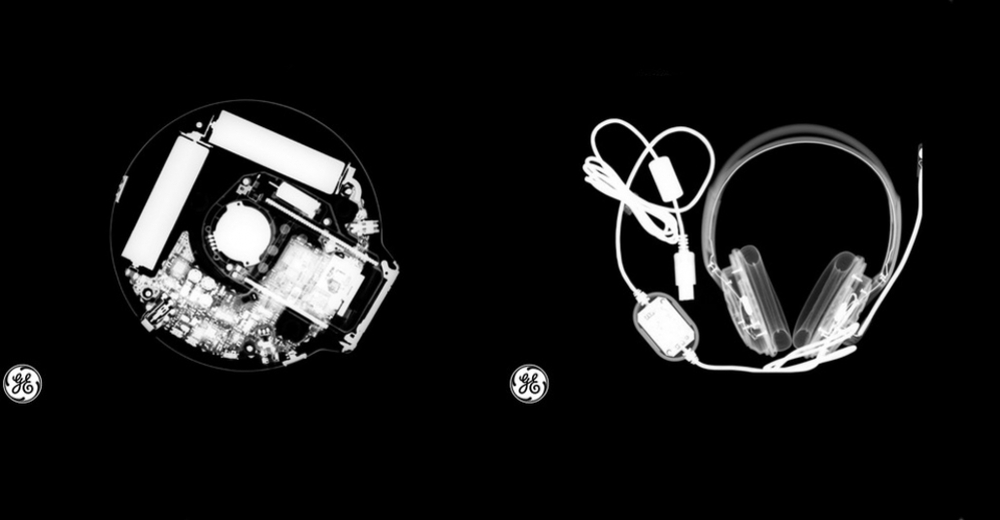

8 Kasım 1895’te Wilhelm Röntgen, deneyleri sonucunda X ışınını buldu. Cisimlerin farklı kalınlıklarla farklı koşullarla hareketini gözlemleyerek mat yüzeyden geçebilen yeni bir ışın keşfetmiştir. Bu teknoloji matematikte bilinmeyeni simgelediği için X ışını ismini alsa da sonradan Röntgen olarak anılmaya başlanmıştır. Bu günün anısına GE Sağlık da #seeinsideit kampanyasıyla gündelik eşyaları; röntgen, bilgisayarlı tomografi ve manyetik rezonans yoluyla taradı.

8 Kasım Uluslararası Radyoloji Günü sebebiyle çekilen fotoğrafların tamamı See Inside It internet sayfasında yer alıyor.

Görsel; SeeInsideIT, CD Çalar ve Kulaklık